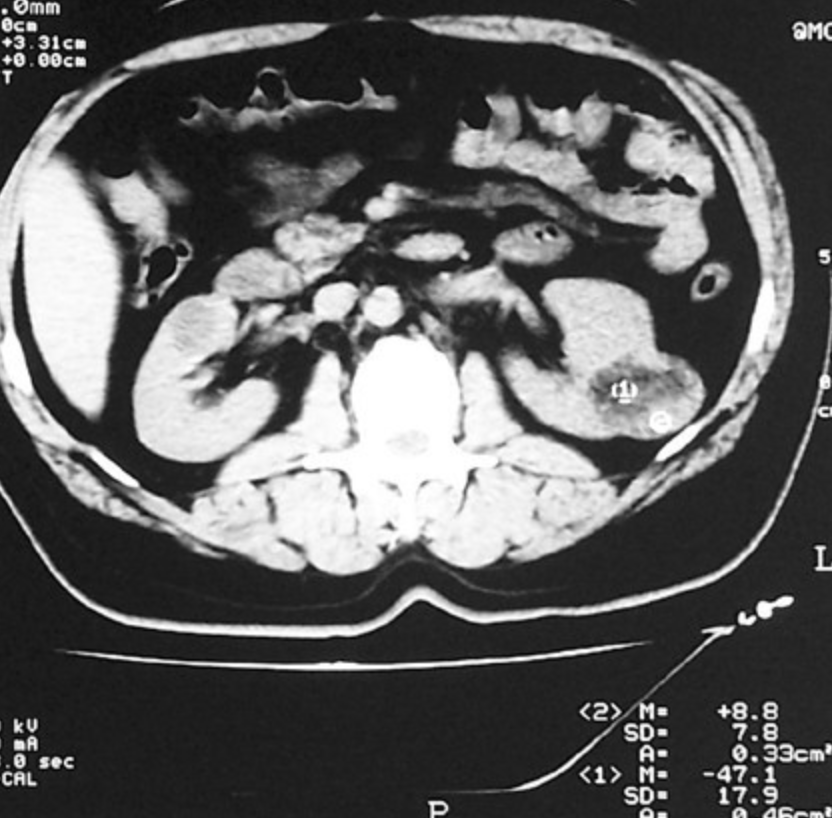

Patiente de 58 ans Douleurs abdominales brutales sans notion de traumatisme Déglobulisation. L'angiomyolipome rénal est une tumeur bénigne solide du rein L'angiomyolipome est la tumeur bénigne la plus fréquente des masses dolides du rein, elle représente un cadre de fréquence de 1 à 3% des tumeurs du rein, sa composition histologique est faite de trois contingents: graisseux, fibres musculaires lisses et vasculaires a des proportions variables, elle sévit sur un cadre sporadique et peut s'exprimer dans un cadre congénitale.

Patiente de 58 ans Douleurs abdominales brutales sans notion de traumatisme Déglobulisation. L'échographie faite chez tous nos patients a retrouvé un aspect hyperéchogène hétérogène dans tous les cas. Il apparaît souvent chez des personnes atteintes de sclérose tubéreuse, un trouble génétique qui engendre la formation de tumeurs non cancéreuses dans de nombreux organes, dont les yeux, la peau, le cerveau, les poumons, le cœur et les reins.